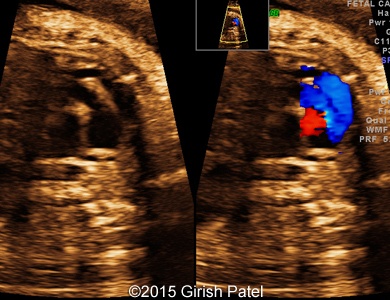

Following images and videos show a case of double inlet left ventricle with transposition of the great arteries that was seen at 26 and 36 weeks of otherwise non-complicated pregnancy.

Images 5, 6, 7: 2D color Doppler images showing the heart with double inlet left ventricle and transposition of the great arteries. Image 5 shows filling of the left ventricle via separate mitral and tricuspid valves (doubled red flow). Images 6 and 7 shows parallel arrangement of the aorta and pulmonary artery (blue flows).

Images 8, 9, 10: 2D gray scale and color Doppler images showing the heart with double inlet left ventricle and transposition of the great arteries - the images 8 and 9 show mitral and tricuspid valves opened to the left ventricle. The image 10 shows branching of the pulmonary artery (RPA, LPA), arising from the dominant left ventricle.